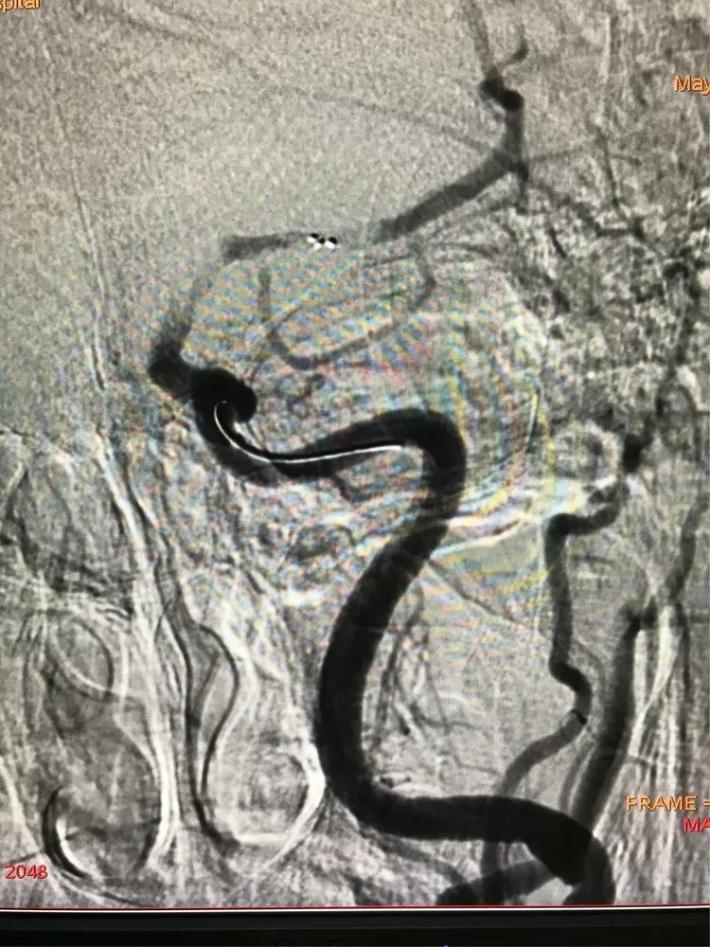

MRA显示:左侧颈内动脉闭塞。

手术步骤

立即桥接取栓,造影显示:左侧颈内动脉闭塞。

右侧颈内动脉向左侧没有代偿。

椎动脉造影显示后交通动脉没有代偿。

微导管进入左侧大脑中动脉远端真腔。

置入支架。

可见大脑中动脉有血流。

取出支架未见血管开通。

再次置入微导管。

置入支架取栓。

见颈内动脉开通,大脑中动脉远端有血栓逃逸。